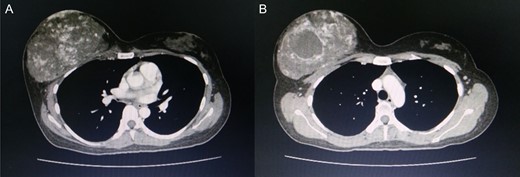

Approximately 2 years ago, a 30-year-old female, with no history of breast surgery, irradiation or pregnancy, presented with a spontaneous, non-symptomatic, hypervascular skin lesion measuring 2 × 2 cm on her right breast. The skin lesion had been gradually increasing in diameter, without any discernable mass or bleeding. Her right breast had undergone rapid enlargement 3 months previously after she had fallen from a motorcycle. A conservative treatment was initially performed using cold compression and analgesic drugs. However, her right breast continued to show progressive enlargement. A physical examination revealed a hypervascular skin lesion measuring 5 × 5 cm on the right breast near the areolar and the large mass was also detected (Fig. 1). The right axillary lymph node was found to measure 1 cm after palpation. A mammogram revealed a large circumscribed hyperechoic mass occupying nearly entire right breast and exhibited multiple internal cystic areas, hypoechoic masses and internal vascularity (Fig. 2). A chest CT showed a hypervascular mass in the right breast measuring 13.7 cm that abutted the pectoralis muscle as well as cystic changes measuring 5.3 cm within the mass (Fig. 3). A metastasis workup was unremarkable, and a fine needle aspiration (FNA) was unable to provide a definitive diagnosis. Therefore, a core needle biopsy was performed on the largest hypoechoic nodule and revealed primary breast angiosarcoma. A right-side total mastectomy was performed with 3 cm margins, pectoralis major muscle resection and axillary lymphadenopathy dissection (Fig. 4). Frozen sections exhibited no malignancies at the margins. A split-thickness skin graft (STSG) was performed, covered and healed well (Fig. 5). The pathology report found poorly differentiated, involving breast parenchyma and the dermis, a tumor measuring 16 cm at its widest axis, a mitotic index of 23/10 HPF, and focal tumor necrosis at 10% of the total tumor volume. All 13 axillary lymph nodes were negative for malignancy (Figs 6–8). No post-operative complications occurred, and no postoperative adjuvants were given.

Computed tomography of the chest revealed a hypervascular mass in the right breast measuring 13.7 cm abutting the pectoralis muscle (A) cystic change measuring 5.3 cm in the mass is visible (B).